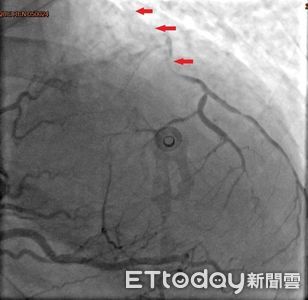

38歲的林小姐是追星族,雖有高血脂及心臟病家族史但平時身體無恙,去年冬天前往演唱會途中,於捷運站內突然喪失意識,站內人員立即協助施行CPR,隨後EMT前往接手急救與電擊,並立即送往急診,一連串急救處置後,經心導管檢查確認為急性心肌梗塞,且三條冠狀動脈都已嚴重阻塞。 《詳全文...》